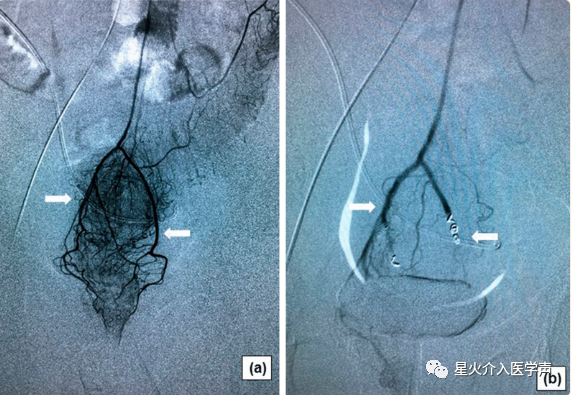

局麻后,采用改良Seldinger法穿刺右股动脉,然后插入4-Fr导管鞘。然后,使用4-Fr Simmons导管(Cordis,迈阿密湖,佛罗里达州)对肠系膜下动脉进行插管,使用2.7-Fr微导管(Terumo,Tokyo,Japan)对SRA及其分支进行超选择性血管造影(图1a,a,2a)。2a)。将适量明胶海绵颗粒(350–560 μm,艾丽康,杭州,中国)或微球(300–500 μm,恒瑞医疗,苏州,中国)注入靶动脉,然后,使用几个2-3 mm金属弹簧圈(美国印第安纳州布卢明顿市)。栓塞剂的总剂量和弹簧圈数由两名介入放射科医师达成共识确定。当痔丛动脉血管床消失后,栓塞术终止(图1b、b、22b)。

图。1内痔患者痔动脉血管造影特征。a使用Simmons导管进行肠系膜下动脉导管插入术,显示直肠血管强化(白色箭头);b最终的动脉造影显示,采用弹簧圈和明胶海绵(白色箭头)栓塞SRA后,直肠下部的血管减少